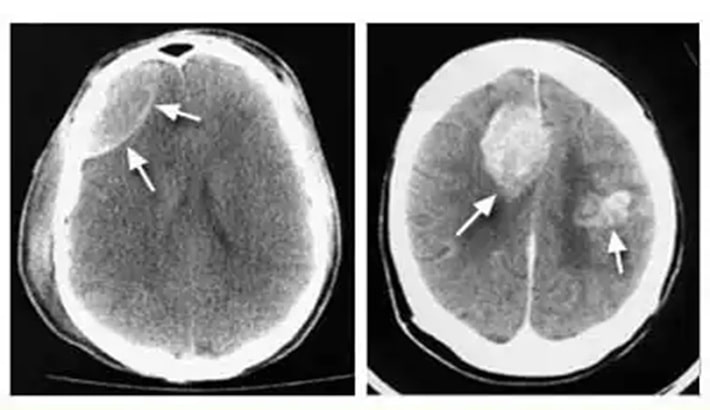

خونریزی مغزی یا هماتوم از خطرناکترین شرایط مغزی است که نیاز به تشخیص فوری و دقیق دارد. در چنین شرایطی، سی تی اسکن مغز بهعنوان سریعترین و قابلاعتمادترین روش تصویربرداری شناخته میشود. این روش میتواند حتی کوچکترین مقدار خونریزی را در عمق بافت مغز یا اطراف آن نشان دهد؛ همچنین پزشک را در انتخاب درمان فوری یاری کند.

نقش سی تی اسکن مغز در تشخیص خونریزی

سی تی اسکن مغز با استفاده از اشعه ایکس و فناوری کامپیوتری، تصاویر دقیق و چندبعدی از بافتهای داخلی مغز تهیه میکند. در این تصاویر، نواحی دچار خونریزی بهصورت روشنتر از بافت طبیعی مغز دیده میشوند. این ویژگی کمک میکند تا نوع و محل خونریزی مغزی بهسرعت مشخص شود.

انواع خونریزیهایی که در سی تی اسکن مغز قابل تشخیصاند:

سی تی اسکن مغز میتواند انواع مختلف هماتوم را از یکدیگر تفکیک کند.

هماتوم اپیدورال:

معمولاً در اثر ضربه شدید به سر ایجاد میشود و بین جمجمه و پرده بیرونی مغز تجمع خون دیده میشود.

هماتوم سابدورال:

خونریزی بین دو لایه از پردههای مغزی رخ میدهد و در تصاویر سی تی اسکن مغز به شکل ناحیهای هلالی دیده میشود.

هماتوم داخل مغزی:

در این نوع، خون درون بافت خود مغز جمع میشود. این حالت معمولاً بهدلیل فشار خون بالا یا پارگی عروق رخ میدهد.

خونریزی زیرعنکبوتیه:

در فضای بین مغز و لایههای اطراف آن اتفاق میافتد و با سی تی اسکن مغز بدون تزریق بهوضوح قابل مشاهده است.